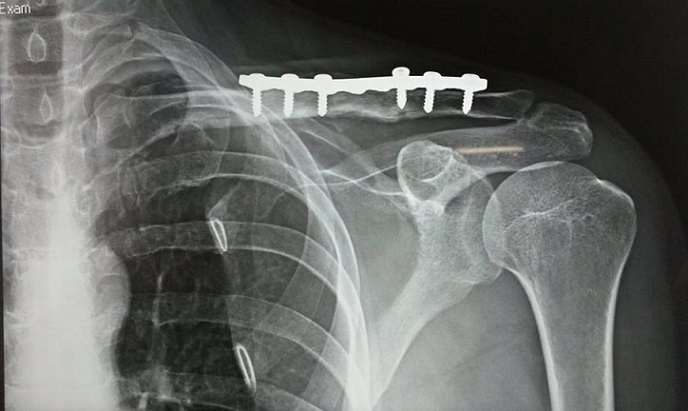

Figure 3: chest radiographs showing callus formation of the fractured clavicle 14 months after the injury with no recurrence of pneumothorax